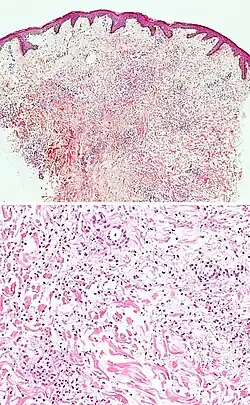

| Urticaria, lymphocyte predominant | Perivascular location. Mast cells are relatively sparse, potentially demonstrated with special stains, preferably tryptase stain. Extravasated erythrocytes are present in about 50% of the cases. No vasculitis.[14] | Dermal edema [solid arrows in (A,B)] and a sparse superficial predominantly perivascular and interstitial infiltrate of lymphocytes and eosinophils without signs of vasculitis (dashed arrow).[15]

|

| Urticaria, lymphocyte predominant | Perivascular location. Mast cells are relatively sparse, potentially demonstrated with special stains, preferably tryptase stain. Extravasated erythrocytes are present in about 50% of the cases. No vasculitis.[14] | Dermal edema (solid arrows) and a sparse superficial predominantly perivascular and interstitial infiltrate of lymphocytes and eosinophils (dashed arrow)